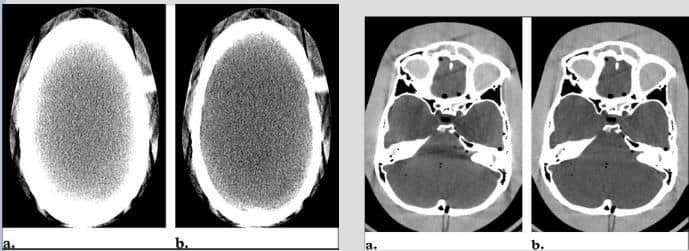

Imágenes corregidas.

Aparece cuando un voxel es ocupado parcialmente por estructuras de distinta densidad radiológica. El ordenador hace la media de ellas apareciendo densidades que no existen en el voxel. Las zonas con tejidos de muy diferente densidad, como la base del cráneo, son típicas para la aparición de este artefacto.